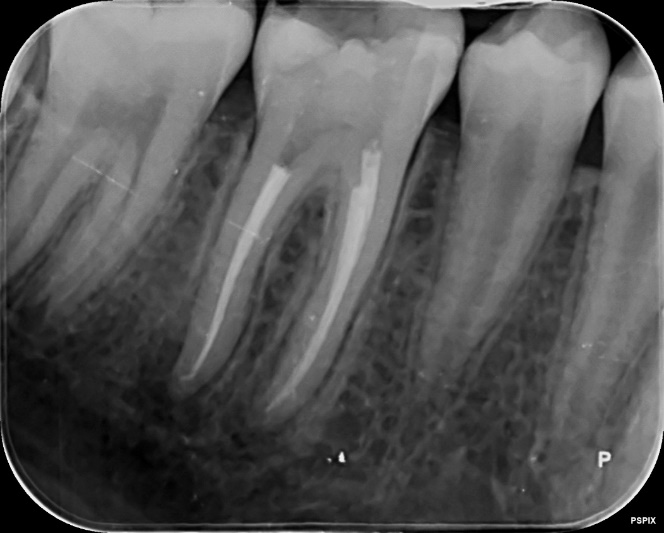

Upper Premolar curved root Primary root canal treatment